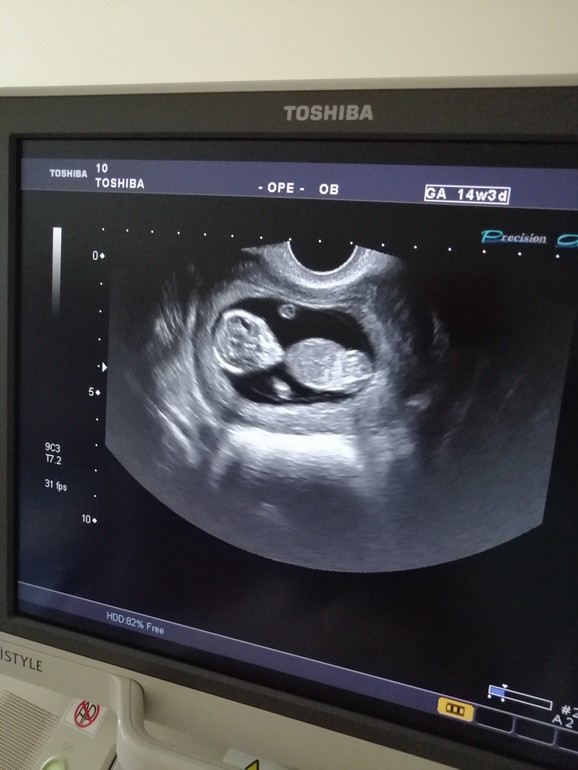

Прошли сегодня первый скрининг.

Врач сказала отличный малыш)

Как считаете, нос и воротниковое пространство хорошие?

Только вот одно смутило, а желточный мешочек разве не должен пропасть к 12й неделе? Я не утверждаю. Это вопрос🤔

Г сказала, что он может до 14 недель быть.